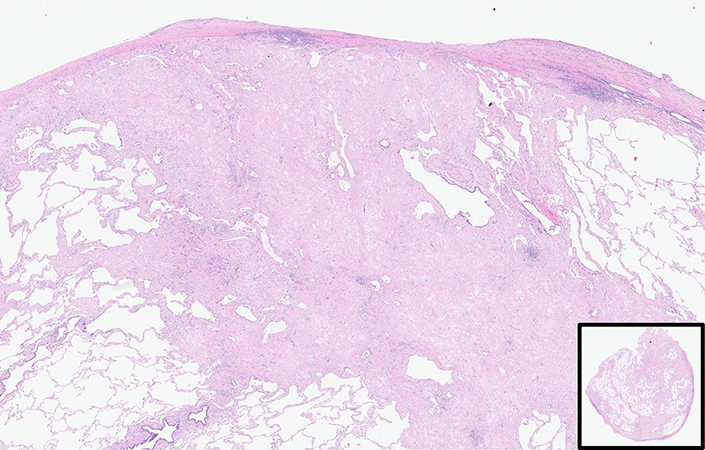

Histopathology shows upper zone pleural thickening with subpleural fibrosis with less or no lower lobe involvement. The combination of visceral pleural fibrosis and intra-alveolar fibrosis is noted in Figure 2. Although it is predominantly seen in a subpleural distribution, deeper extension is seen in Figure 2 with involvement around the bronchovascular bundles (Figure 3) and residual alveolar spaces (Figure 4). Even on the H&E slide, septal elastosis can be appreciated, but elastic van Gieson stain highlights the elastotic nature of the process (Figures 5 and 6). Usual interstitial pneumonia (UIP) may co-exist in the lower lobe as reported in the literature. Current evidence suggests that some patients with PPFE are more likely to develop progressive disease, including the idiopathic types, people with short telomere lengths and concomitant CHP or UIP. Corticosteroids and immunosuppressive agents such as methotrexate or Azathioprine are best avoided due to increase in risk of infections.

Take home message for trainees: Think of PPFE when a combination of visceral pleural fibrosis and extensive intra-alveolar septal elastosis is present.